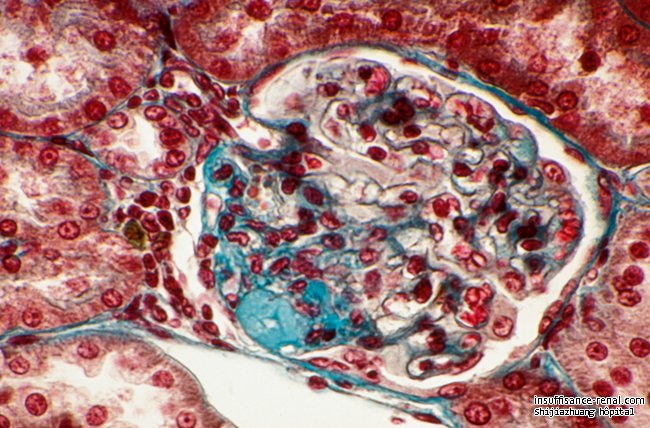

(L'un des très nombreux glomérules qui, dans les reins, participent au renouvellement de l'eau qui compose notre corps.)